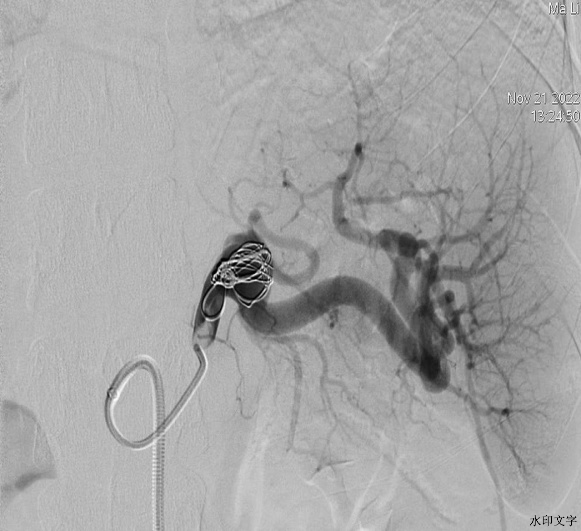

41岁的马女士,因体检发现脾动脉瘤入住我院普外科。普外科邀请介入科赵蔚主任会诊,结合患者脾动脉瘤重建图像,赵主任建议行DSA引导下动脉瘤内微弹簧圈栓塞术。经过详细体格检查、排除手术禁忌症,次日,赵主任和主治医师代福联合为该患者行局麻下腹腔动脉造影检查,造影示动脉瘤位于脾动脉近段,以6F超长血管鞘引入5F肝动脉导管于动脉瘤体近端,以2.7微导管于动脉瘤腔内反复盘旋后释放1枚带纤毛微弹簧圈(14mmx50mm),造影复查再次填补1枚(6x10mm)普通微弹簧圈后动脉瘤体内未见明显血流,脾动脉主干血流未见受损,栓塞效果满意。术后患者生命体征平稳,现已康复出院。